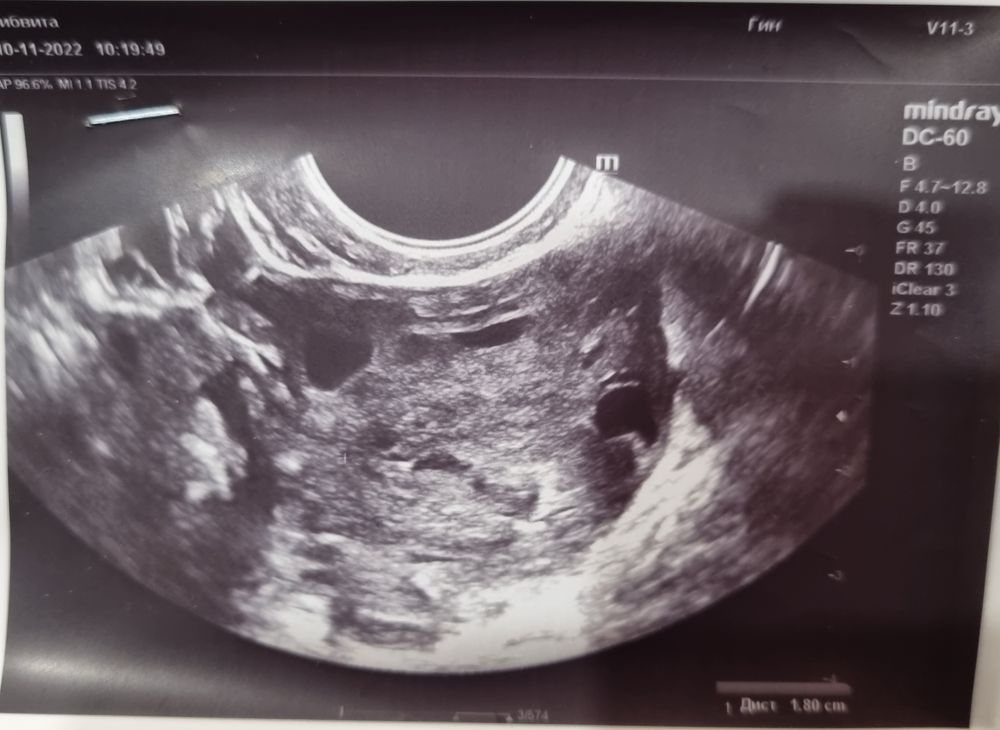

Эндометрий очень неоднородный на 1 фото. 2 фото желтое тело скорее всего. 3 киста фолликулярная. Дюфастон допивайте, на отмене придут месячные. На 5-7 день цикла я бы эндометрий пересмотрела на предмет полипов. Нехорошо выглядит он у вас

На последнем фото ,похоже на фолликулярную кисту ,у меня она была.Это не страшно.

Может к другому узисту пойти? Скорее всего овуляции не было или очень поздняя была от этого и задержка.Цикл же от овуляции зависит.

Анастасия , Эндометрий маловат для начала месячных конечно.Ну и если жт есть,то овуляция была,может было 2 фолликула доминантных и один не лопнул ,либо все же поздняя овуляция.

Просто по фото последнему у меня точно так же было ,я 2 месяца с этой кистой ходила и мониторила её рост,потому что была еще и беременность. Поэтому эту фотку точно узнаю😅Но могу и ошибаться🤷🏼♀️